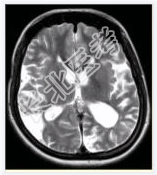

- [材料题] 女性,22岁。癫痫发作及智力异常。MRI显示见下图。